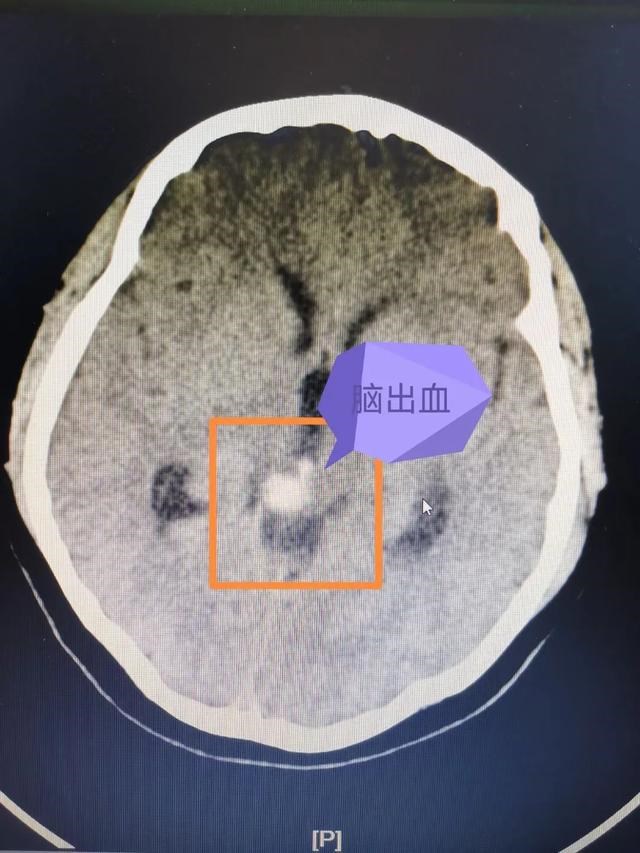

经过头颅CT检查,接诊的巴特尔副主任医师发现大梅存在着非常危险的脑干出血,对于没有高血压病史的年轻患者,他立即想到了脑血管疾病的可能性,于是很快进行了头颅MR检查,发现脑干出血周边有可疑的异常脑血管影,初步确定了之前的推测。

脑血管畸形是一种先天性的脑血管疾病,脑出血是脑血管疾病最常见的发病表现。已经有过出血的脑血管畸形随时有再次破裂的风险。而核桃大小的脑干是生命中枢,掌管着人体的呼吸、心跳、体温等最基础的功能。脑干出血属于脑出血中最危险的一种,通常情况下,哪怕是2~3毫升的脑干出血都可能引起严重后果,一旦出血量超过5毫升,死亡率高达70%以上。大梅的生命危在旦夕,却又无法长途转运。而且脑干周围的脑血管畸形的治疗极其复杂,风险极高,如何成功“拆弹”、挽救患者的性命,巴特尔医生心里没底。